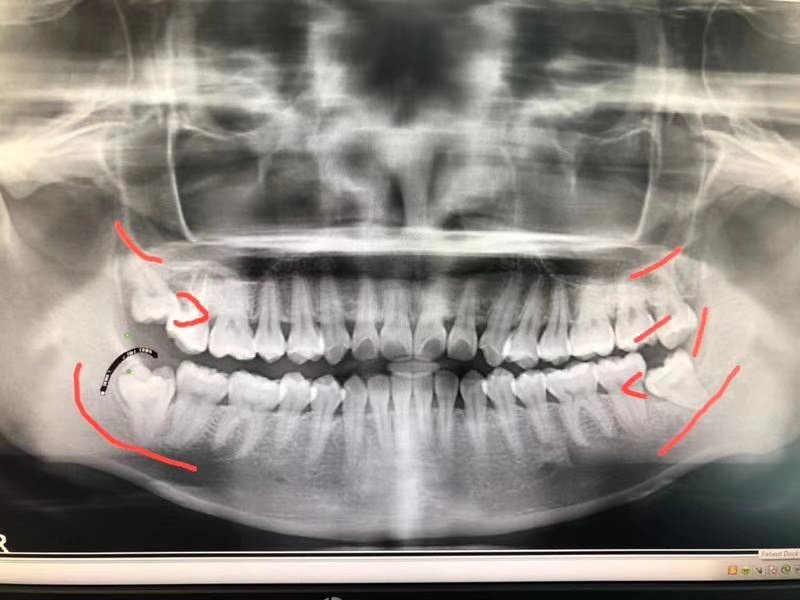

我的智齿状况

我有三颗阻生牙。其中左下是completely bony,被困在牙龈和颚骨之间,进食后非常容易有残余塞在牙龈和牙齿的缝隙,导致疼痛。左上和右下是Mesial impaction,内侧向阻碍,左上比较严重的是很有可能一直在磨损我做过牙髓治疗的大牙(没来得及做牙冠)。右上是最简单的智齿,但是比大牙偏长,拔完下面的智齿后,向下咬合时上面的智齿会容易咬到牙龈。

所以牙医建议全部去除。嗯,听上去很有道理,同意。